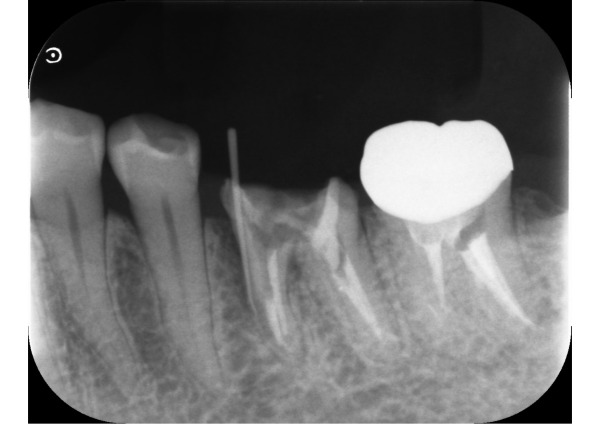

お口の中を見てみると、左下6番目の歯ぐきにサイナストラクト(歯根の炎症が原因でできる、膿の出口となる穴)が認められました。口腔内エックス線画像から、残っている歯根が薄いため、破折している可能性をお伝えしました。

歯根の状態をさらに詳しく調べるため、セラミックを外してサイナストラクトに造影性のあるゴムを挿入し、再度、口腔内エックス線検査を行いました。破折した部位からの細菌感染により、歯根に沿って深く骨がなくなっていました。また、口腔内カメラで破折した部位を確認し、保存は難しく、抜歯となりました。

5日目〜8日目 サイナストラクトを認めたため、デンタルエックス線を撮影し、歯根破折の疑いがあると説明しました。セラミックを外して破折した部位を確認するため、造影性のあるゴムを写して再度撮影しました。